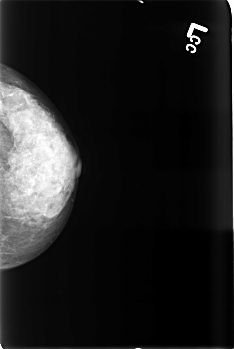

B_3437_1.LEFT_MLO

B_3437_1.LEFT_CC

LEFT_MLO LINES 4424 PIXELS_PER_LINE 2992 BITS_PER_PIXEL 12 RESOLUTION 50 NON_OVERLAY

LEFT_CC LINES 4536 PIXELS_PER_LINE 3032 BITS_PER_PIXEL 12 RESOLUTION 50 NON_OVERLAY